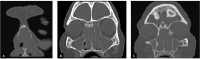

Woakes' syndrome (WS) is a rare entity, defined as severe recalcitrant nasal polyposis with consecutive deformity of the nasal pyramid. WS occurs mainly in childhood and its aetiology remains unclear. We report a case of a 68-year old woman, with aspirin-exacerbated respiratory disease, who presented with recurrent nasal polyposis and progressive broadening of the nasal dorsum. CT scan revealed extensive bilateral nasal polyposis and diffuse osteitis, with anterior ethmoidal calcified lesions. The patient underwent revision endoscopic sinus surgery and nasal pyramid deformity was successfully managed without osteotomies.